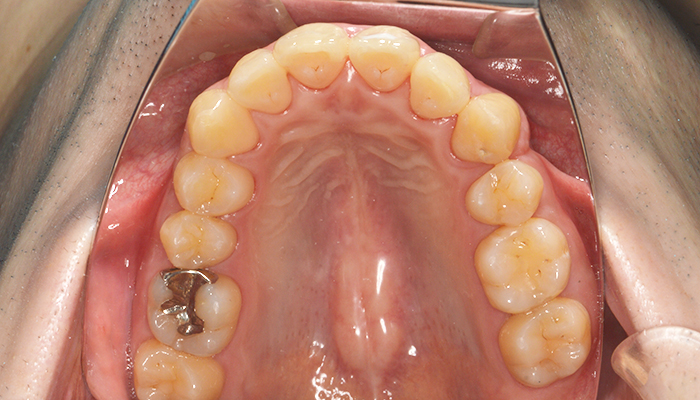

実際の患者様のお口の状況を知るために、口腔内写真、顔面写真、レントゲン撮影、上下顎模型印象、噛み合わせ確認、歯周病検査、デジタル印象などを行なっていきます。4番の抜歯(1本)

上の片側4番目の歯を1本抜歯しました。その他の健康な歯は抜歯していません。(親知らずは抜歯しています)

ワイヤーだと片側抜歯を行うと正中のラインが抜歯した方向へ流れてしまうことがありますが、今回はマウスピース型矯正装置(インビザライン)で行ったため、そのような反作用は生じませんでした。